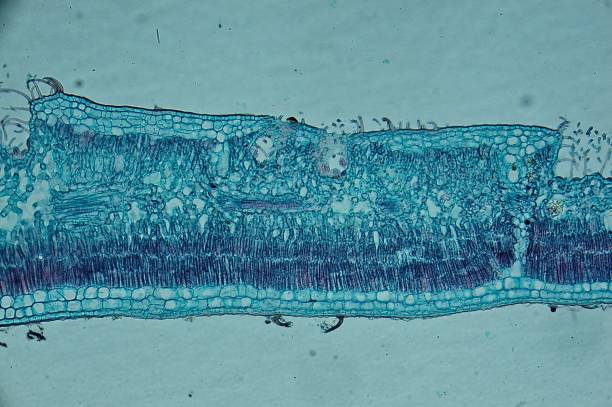

• 組織工程和生物材料:組織工程是體外開(kāi)發(fā)或生長(zhǎng)組織和器官以替換或支持有缺陷、患病或受傷的身體部位的功能,或定向管理體內(nèi)或體內(nèi)組織的修復(fù)。組織工程是一個(gè)關(guān)鍵平臺(tái),它使用生物相容的支架植入體內(nèi)新組織形成的位置。如果支架具有需要再生或恢復(fù)的組織的幾何形狀,支架會(huì)吸引細(xì)胞,從而產(chǎn)生所需形狀的新組織。如果新形成的組織在形成時(shí)能夠鍛煉,那么新的功能工程問(wèn)題將取得成功。組織工程目前用于以下領(lǐng)域: